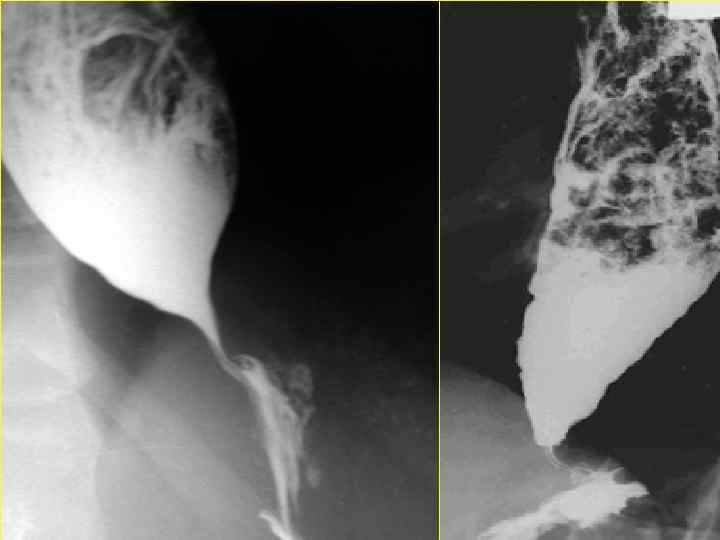

АНОМАЛИИ РАЗВИТИЯ МОЧЕПОЛОВОЙ СИСТЕМЫ

Иссечение кисты и обработка внутренней ее выстилки